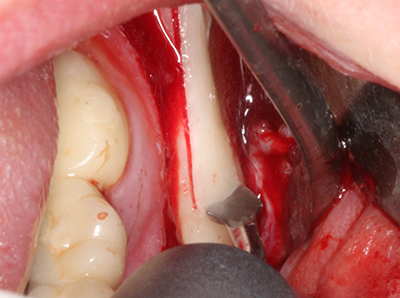

Фиг. 19: Хирургичното поле след невролиза и отстраняване на остеотом.

Фиг. 20: Отстраненото костно покритие е поставен отново и фиксиран с винт за остеосинтеза (KLS Martin, Tuttlingen).